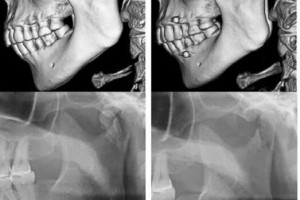

髁突骨折是颌面部较常见的骨折类型之一,占下颌骨骨折的25%~35%。对于髁突骨折的调节,虽然在临床上有很大争议,但开放复位内固定仍是多数髁突...